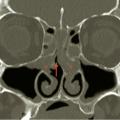

Le dysfonctionnement nasal chronique d’une allergie aux acariens peut se rapprocher de celui d’une rhinite non allergique à éosinophiles ou d’une polypose nasale mais la fibroscopie nasale ne trouve pas de polypes francs des méats moyens ou des fentes olfactives. Elle objective seulement un aspect œdémateux, parfois même pseudo- polypoïde, de la tête ou du bord libre des cornets moyens, associé à une hypertrophie blanche, rouge ou lilas des cornets inférieurs, par ailleurs tapissés de sécrétions séreuses ou muqueuses qui peuvent s’accumuler sur le plancher nasal. Une tomodensitométrie doit alors compléter la démarche diagnostique. Dans la rhinite chronique aux acariens, les masses latérales de l’ethmoïde et les sinus paranasaux montrent une radiotransparence normale alors que l’essentiel des signes pathologiques sont retrouvés au niveau du nez respiratoire (qui ne fait actuellement l’objet d’aucune description dans les comptes-rendus radiologiques) [fig. 2 ]. C’est donc la concordance des signes nasofibroscopiques et tomodensitométriques qui contribue au diagnostic des rhinites respiratoires chroniques. L’origine allergique, toujours recherchée, n’est cependant pas systématiquement retrouvée.7

Le dysfonctionnement nasal chronique d’une allergie aux acariens peut se rapprocher de celui d’une rhinite non allergique à éosinophiles ou d’une polypose nasale mais la fibroscopie nasale ne trouve pas de polypes francs des méats moyens ou des fentes olfactives. Elle objective seulement un aspect œdémateux, parfois même pseudo- polypoïde, de la tête ou du bord libre des cornets moyens, associé à une hypertrophie blanche, rouge ou lilas des cornets inférieurs, par ailleurs tapissés de sécrétions séreuses ou muqueuses qui peuvent s’accumuler sur le plancher nasal. Une tomodensitométrie doit alors compléter la démarche diagnostique. Dans la rhinite chronique aux acariens, les masses latérales de l’ethmoïde et les sinus paranasaux montrent une radiotransparence normale alors que l’essentiel des signes pathologiques sont retrouvés au niveau du nez respiratoire (qui ne fait actuellement l’objet d’aucune description dans les comptes-rendus radiologiques) [